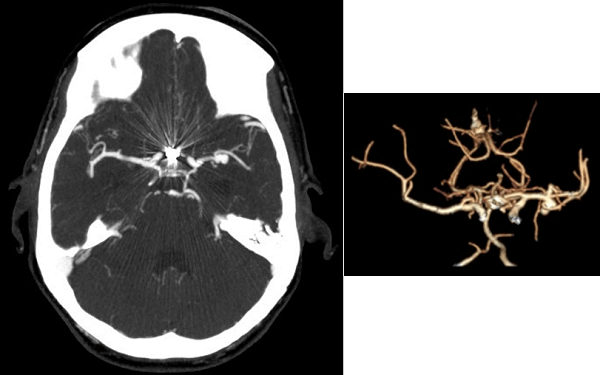

History : 45 year old man with sudden onset of severe headache.

What is the most likely etiology for this patient’s intraventricular hemorrhage?

Answer: MCA Aneursym. The images demonstrate an intensely vascular mass in the right supraclinoid region. The mass appears to communicate with the adjacent vasculature and is most consistent with an aneurysm.

(A) axial CTA head demonstrates a distal left middle cerebral artery (MCA) aneurysm

(B) shaded surface display (SSD) reconstruction demonstrates the 3 dimensions of the M1 segment aneurysm which incorporates the origin of the inferior division of the M2 segment (blue arrow)

Ruptured aneurysms typically produce subarachnoid hemorrhage associated with a classic clinical presentation – the thunderclap headache or worst headache of a patient’s life. However, depending on their location, aneurysms can also selectively dissect into the brain parenchyma (proceeding intracranial hemorrhage) or into the ventricles (intraventricular hemorrhage) as in this case.